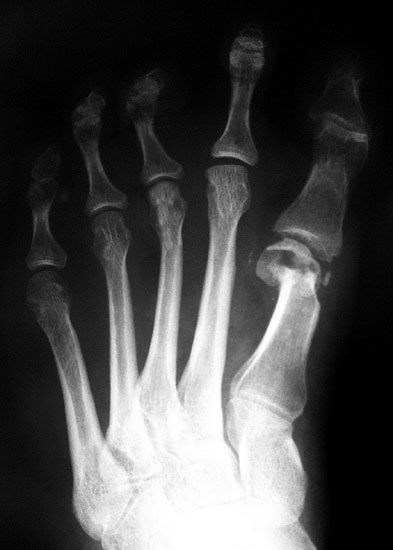

Die Röntgenaufnahmen (Abbildung 1) zeigen den Fuß einer 34 jährigen Patientin nach Exostosenabtragung. Der erhöhte intermetatarsale Winkel wurde durch eine alleinige Abtragung der Exostose nicht reduziert. Als weiterer Risikofaktor für ein Rezidiv liegt ein pathologischer Gelenkwinkel vor. Der intermetatarsale Winkel von 18 Grad kann durch eine basisnahe Osteotomie gut korrigiert werden. Da durch die gleichzeitige distale Korrektur des Gelenkflächenwinkels mithilfe einer Reverden-Green Osteotomie ein Längenverlust von ca. 2-4 mm einhergeht, bot sich als proximales Korrekturverfahren die basisnahe Open-wedge Osteotomie an, um bezüglich der Länge des Metatarsale I neutral zu bleiben (Abbildung 2). Die Kombination zweier verkürzender Verfahren (z.B. Lapidus und Reverden-Green) würden zu einem sehr kurzen ersten Strahl führen, mit dem Risiko einer Transfermetatarsalgie. Übersteigt die Verkürzung des Metatarsale I 2 mm, steigt das Risiko für die Entwicklung einer Transfermetatarsalgie deutlich an 8. Die durchgeführte Revision zeigt eine gute Stellung des 1. Strahls bei zentriert stehendem Gelenk.